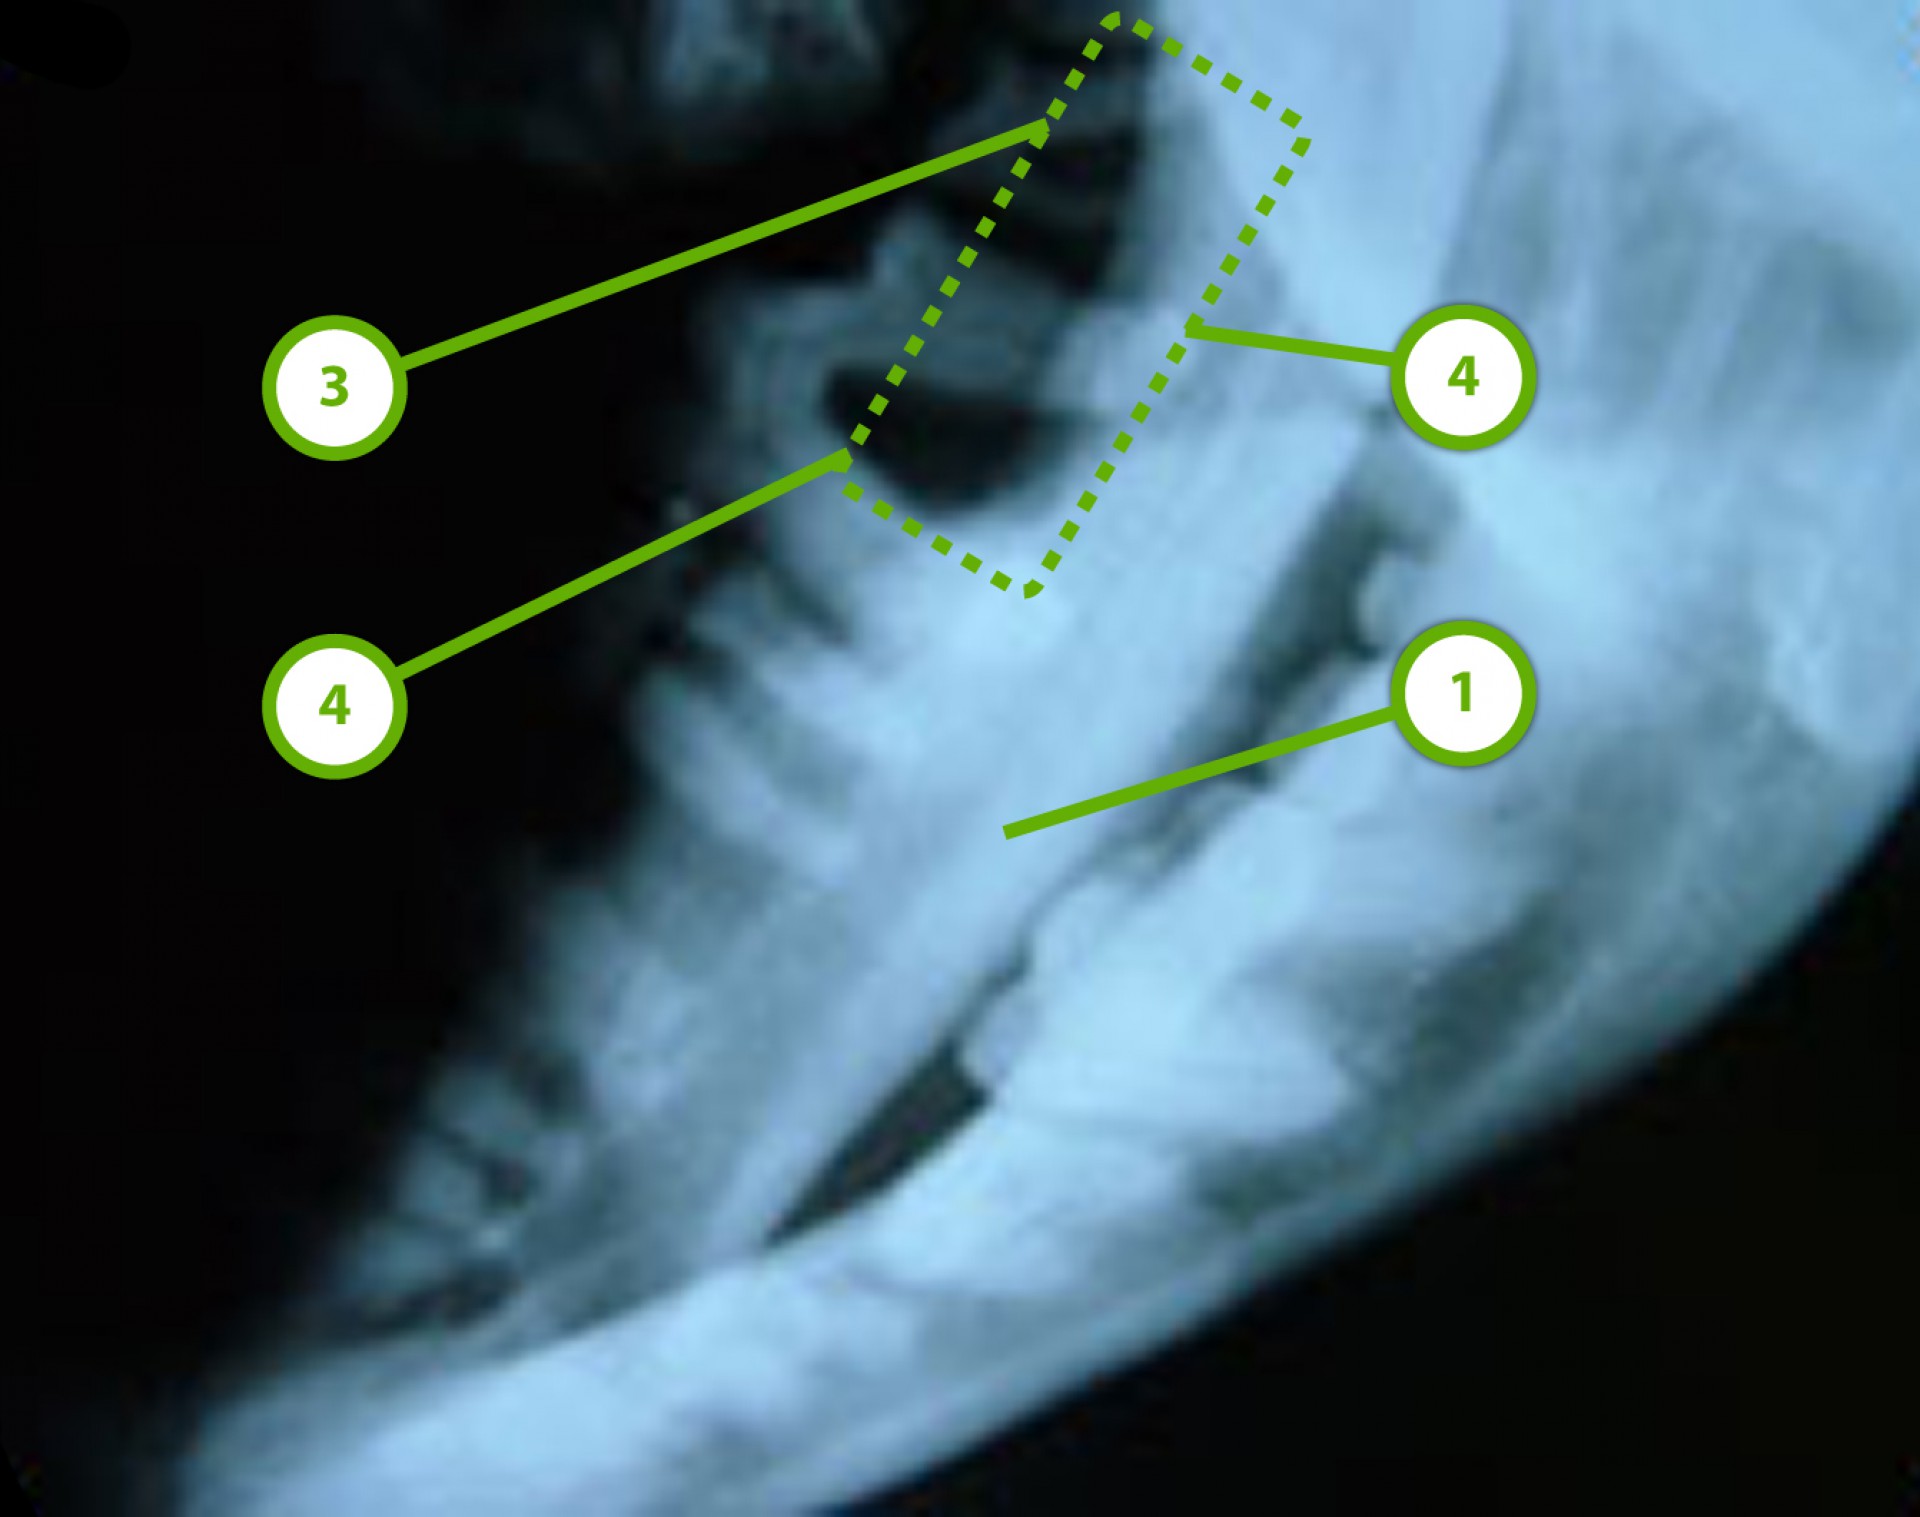

• a szájüreg csontozatának röntgen vizsgálata,

A rosszindulatú daganatok általában nemcsak a lágy szövetekben okoznak elváltozást, hanem az alattuk található csontozatban csontoldó folyamat (osteolysis), a regionális vagy távoli nyirokcsomókban, a mellkasban, hasüregben áttét mutatható ki.

Az állkapocs környéki rosszindulatú daganatos elváltozások általában az állkapocs egyik szárát érintik, így a daganat eltávolításával együtt az érintett állkapocsrész is eltávolítandó (hemimandibulectomia). Az állkapocs egyik oldali szárának eltávolítását követően az azonos oldali pofák plasztikai jellegű igazítására is szükség van (cheiloplastica), mely a táplálékfelvételt segíti ill. a nyálcsorgást akadályozza meg.